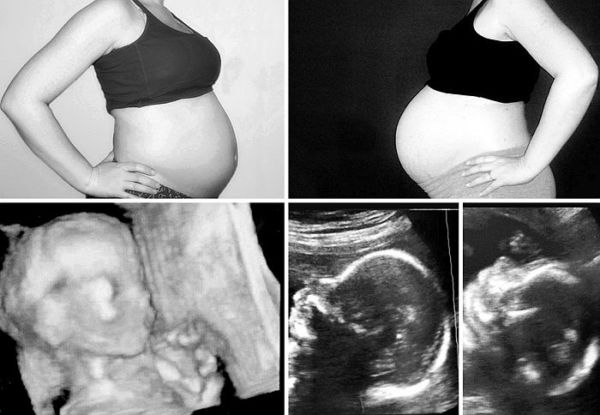

Οι φωτογραφίες αυτές δείχνουν τις διαφορές στο μέγεθος της κοιλιάς μου, στις δύο εγκυμοσύνες μαζί με τους υπερήχους των αντίστοιχων εβδομάδων.  Ακόμα δεν μπορούμε να πιστέψουμε με τον σύζυγό μου όλα όσα έχουμε περάσει για να αποκοτήσουμε αυτά τα τρία υπέροχα παιδιά που έχουμε σήμερα. Παρ όλες τις αγωνίες, τις απογοητεύσεις (από τις αποτυχημένες προσπάθειες) και τα άγχη μας, δεν θα αλλάζαμε τίποτα.Τα τρία μου παιδιά, 5 και 2,5 ετών πια, είναι όλος μας ο κόσμος και αληθινά θαύματα της ζωής, που δεν θα υπήρχαν χωρίς τις απίστευτη εξέλιξη στην ιατρική. Γι’ αυτό, είμαι αληθινά ευγνώμων.»